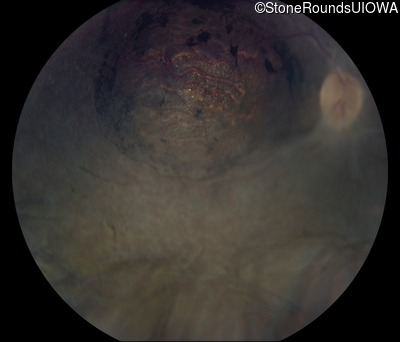

Fundus Montage - Right - Light Perception

Exemplar